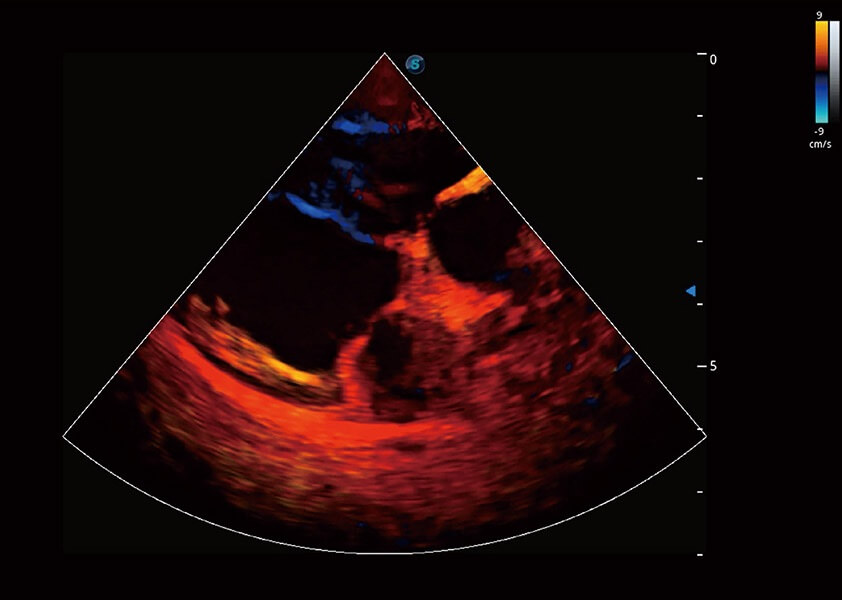

ProPet 60 作为一款高端台式动物超声设备,为动物医生的日常诊断提供了一系列贴合动物临床需求、解决临床实际问题的高级成像功能。凭借全系列高清探头,满足医生对腹部、心脏、生殖、浅表、肌骨等成像的所有需求,切实帮助您提升检查效率,提高诊断信心。

动物是人类最亲密的朋友和最值得信赖的伙伴。竞技宝(JJB)官方网站也一直致力于探索动物专用的超声影像解决方案。 全新推出的ProPet系列,是竞技宝(JJB)官方网站在动物超声影像智能化、专业化、精准化的一次跨越式革新。动物不能用言语来表述自己的不适,通过超声影像,ProPet系列搭建了动物医生与不同物种沟通的“桥梁”,为动物医生注入了“治愈之力”。